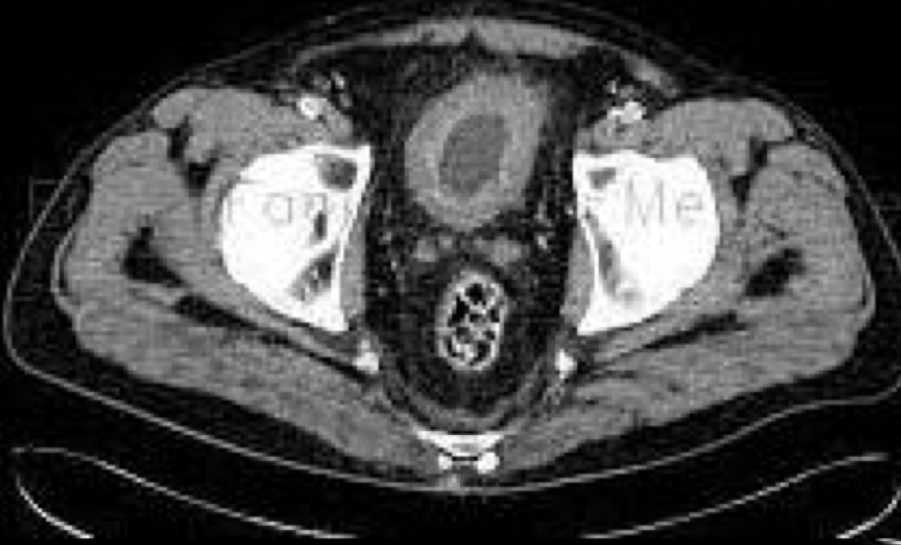

Que se ve en tc de la cistitis

A

• paredes engrosadas

• Burbujas en pared: cistitis enfisematosa: DM2. Xq bacterias anaerobias llenas de gas

• Capta contraste